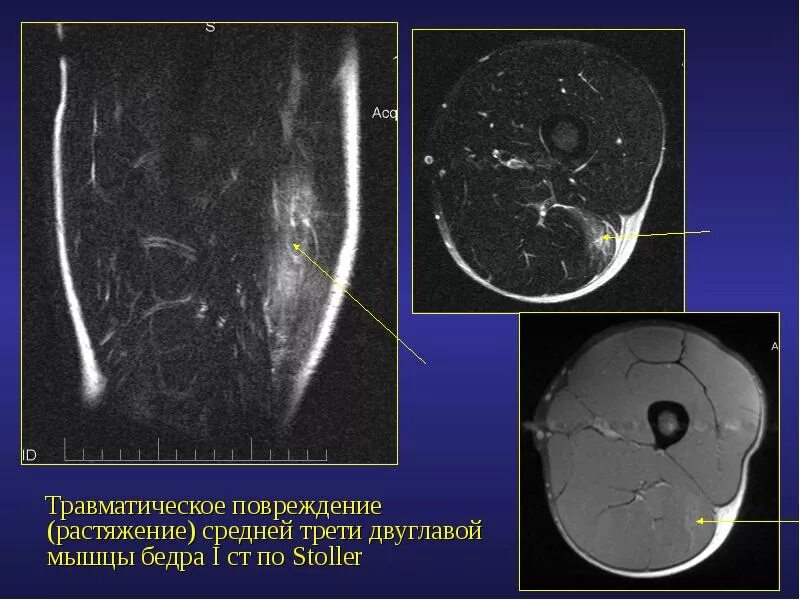

Повреждение внутренних тканей